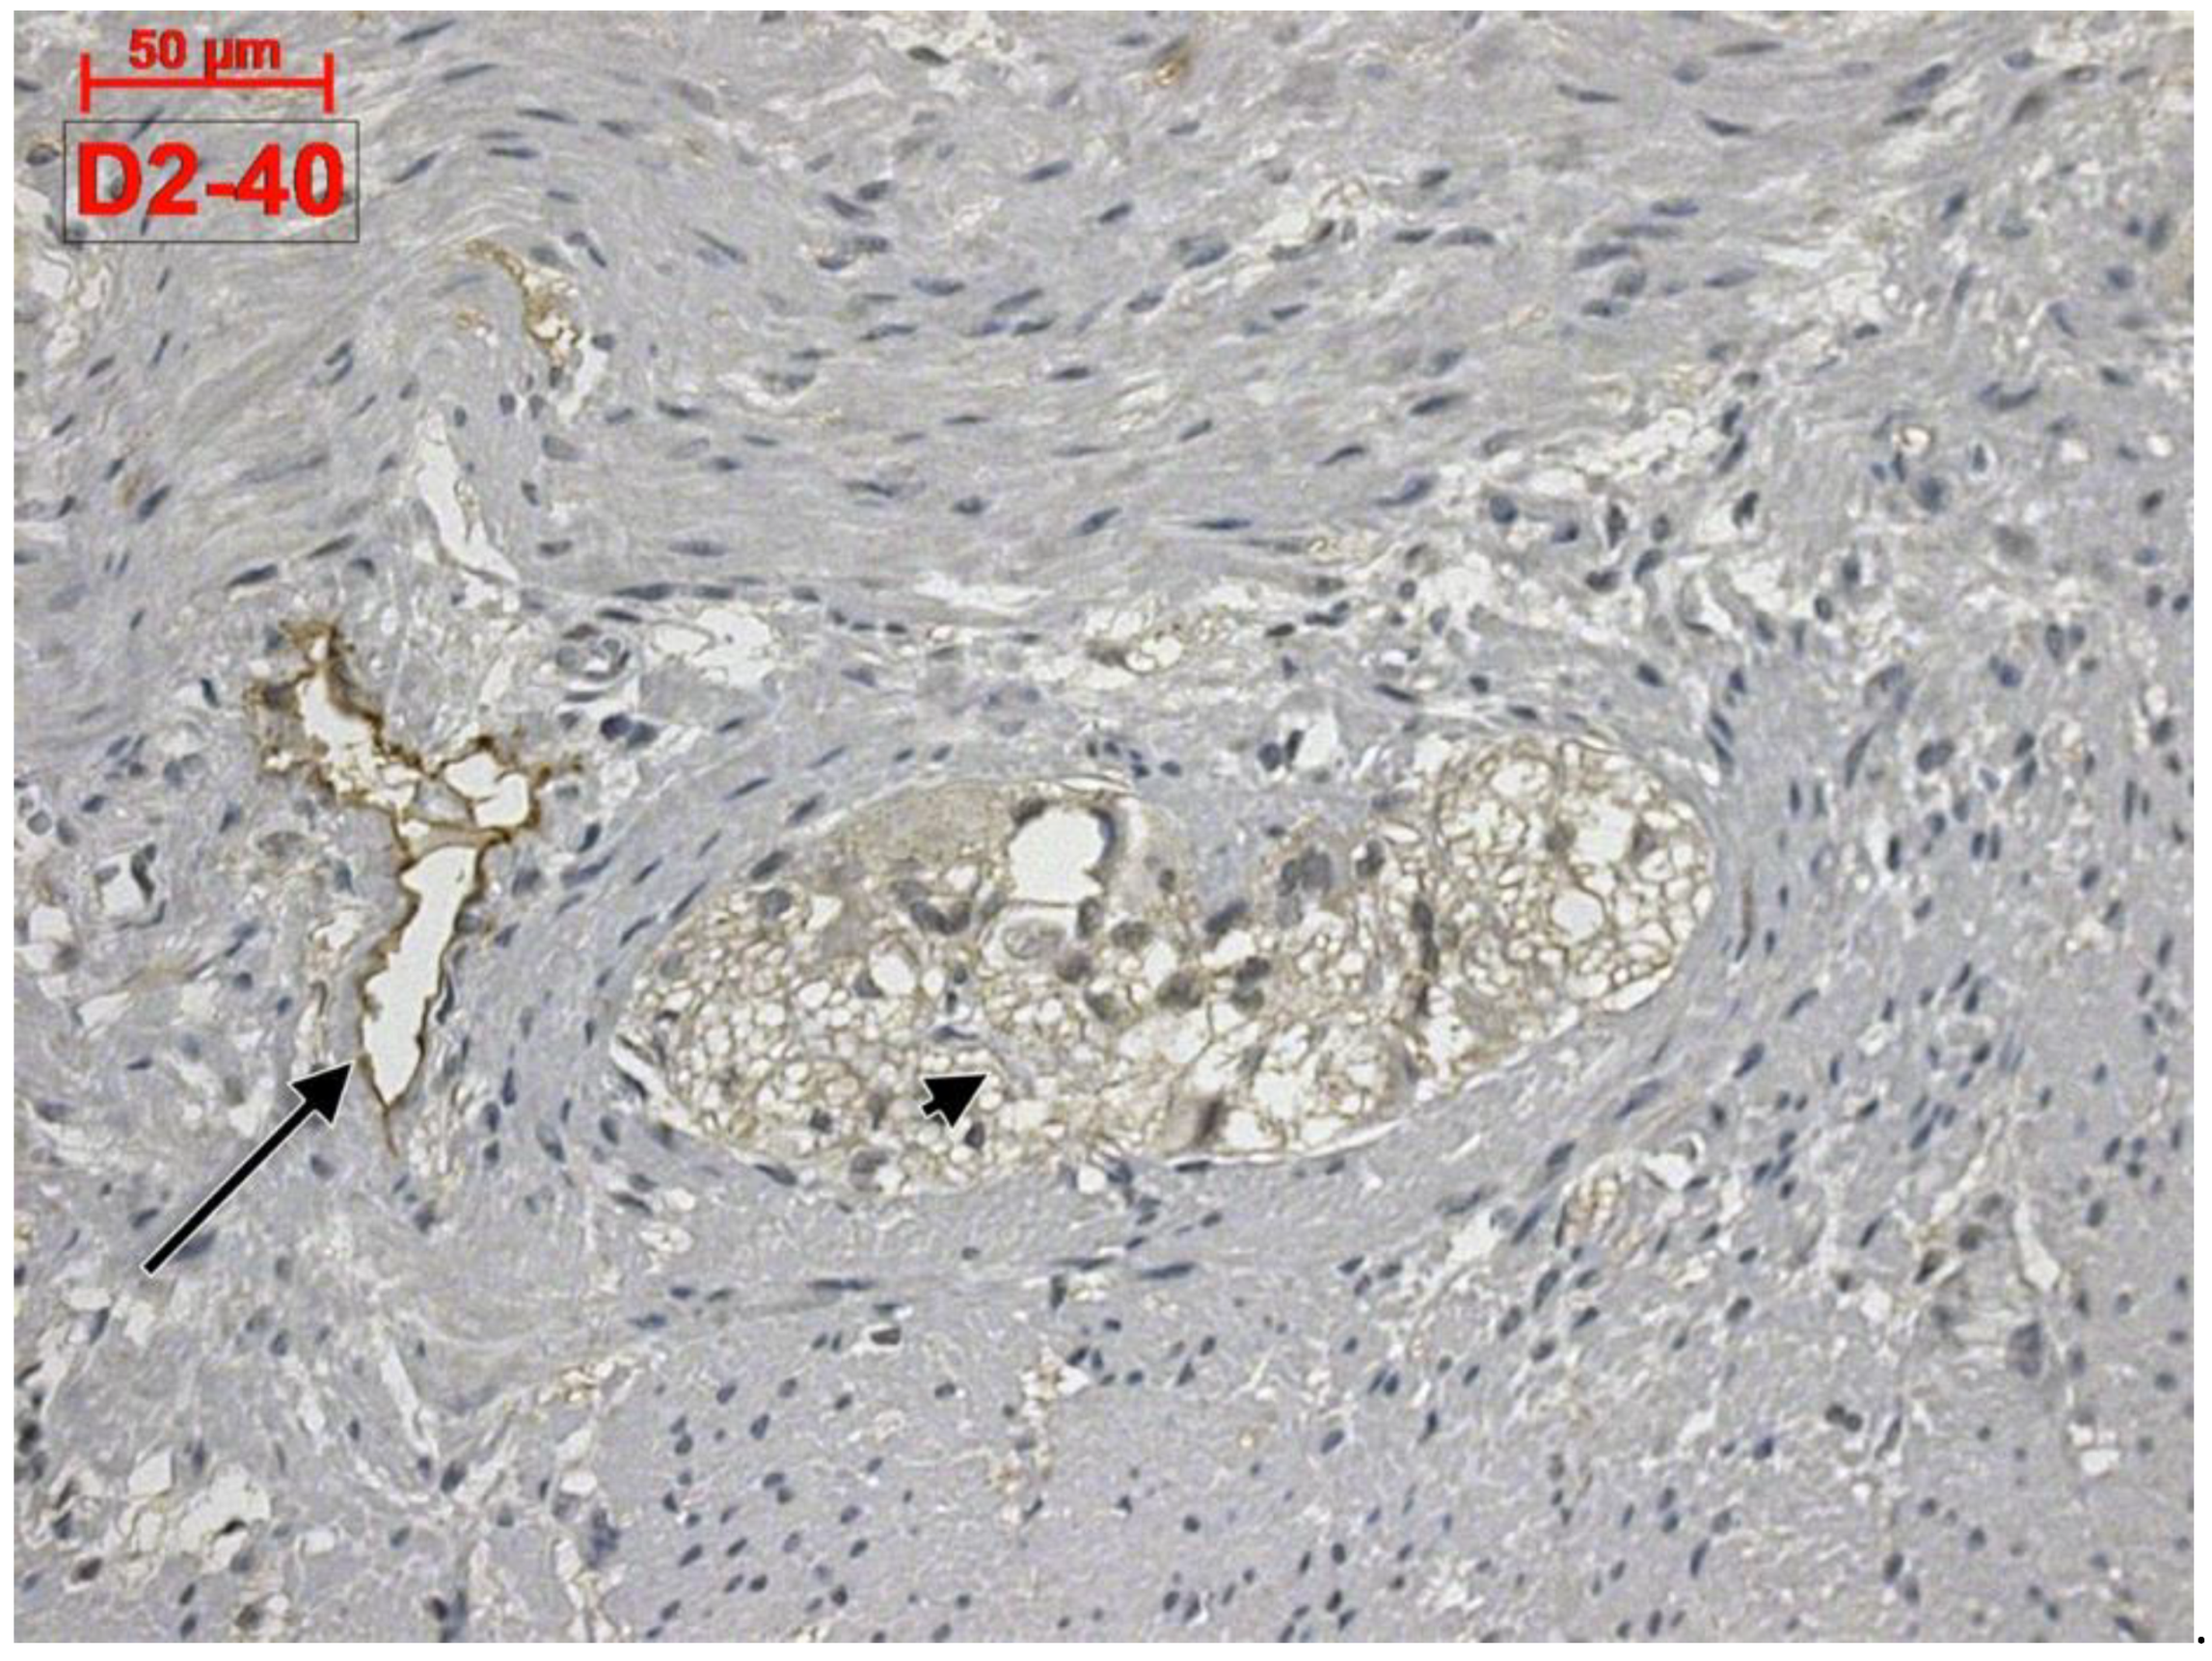

Telocytes and Lymphatics of the Human Colon